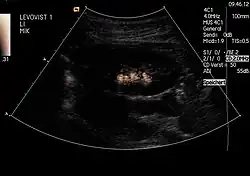

Im Ultraschallfeld beginnen Mikrobläschen zu oszillieren. Bei höheren Schalldrücken entstehen auch nichtlineare Schwingungen hoher Amplitude, die gut von Signalen des Gewebes getrennt werden können und es so ermöglichen, die Blutversorgung von Gewebe zu beobachten.

- Mikrobläschen bei steigenden Schalldruck-Amplituden des Ultraschalls

-

Ultraschall wird linear zurückgestreut -

Ultraschall wird nichtlinear zurückgestreut -

Das Mikrobläschen wird zerstört